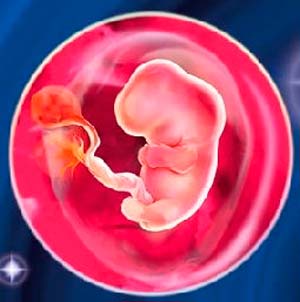

Les plus grandes parties du corps sont la tête et le torse. Les bras et les jambes sont de minuscules processus avec des tubercules-doigts. La taille du fœtus (plus précisément, l'embryon) dans la 6ème semaine d'obstétrique atteint 4 mm, poids - jusqu'à 2 g. Mais comment se passe son développement:

- les membres s'allongent progressivement, les courbes des genoux et des coudes sont décrites;

- les doigts poussent un peu;

- les structures cartilagineuses se développent, c'est-à-dire les os futurs;

- la formation du cerveau commence, la moelle osseuse est à ses balbutiements;

- les organes génitaux externes sont à peine esquissés;

- l'oreille interne commence à se développer;

- le thymus (glande thymus) est formé, l'organe d'immunité le plus important;

- les poumons, le cœur, le foie, l'estomac et le pancréas continuent de se développer;

- le tube neural devient le système nerveux embryonnaire;

- le tissu musculaire se développe encore rapidement.

Le petit cœur compte régulièrement environ 140 battements par minute. Est-ce beaucoup ou peu? Il existe une telle loi dans la nature - plus le cœur d'une créature vivante est petit, plus il bat vite. Par conséquent, une telle «impulsion» dans l'embryon est dans l'ordre des choses. Jusqu'à présent, seul un spécialiste peut déterminer le rythme cardiaque lors d'une échographie.

Et voici un nouveau miracle - le placenta se développe, le cordon ombilical se forme. Le bébé n'est plus pressé près de la paroi de l'œuf fœtal. Il nage librement dans le liquide amniotique et fait ses premiers mouvements. Mais la mère ne pourra pas le ressentir très bientôt. Mais elle se sent beaucoup plus.